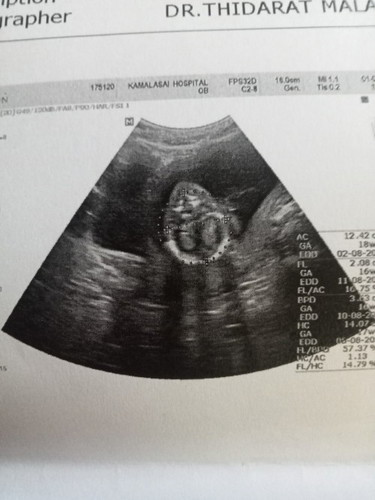

18วีคค่ะ ไปอัลตราซาวด์มา ถามเพศคุณหมอ หมอไม่บอกค่ะ

ช่วยดูให้หน่อยค่ะ ผู้หญิง หรือผู้ชาย แม่ลุ้นมากค่ะ ทองเเรกค่ะตื่นเต้นมาก